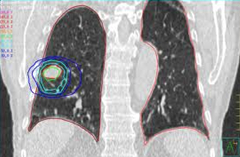

早期肺癌利用IMRT+IGRT

作立體定向電療